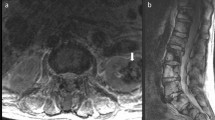

8.3% (n = 267) of children featured at least one IF. One or more musculoskeletal IFs were found in 7.9% (n = 254) of children, however, only 0.8% (n = 2) of musculoskeletal IFs required clinical evaluation. Most frequent abnormalities were simple bone cysts 6.0% (n = 195), chondroid lesions 0.6% (n = 20), and perineural cysts 0.5% (n = 15). Intra-abdominal IFs were detected in 0.5% (n = 17) of children, with over half (n = 9) of these requiring evaluation. The three most common intra-abdominal IFs were a duplex collecting system 0.09% (n = 3), significant ascites 0.06% (n = 2), and hydroureteronephrosis 0.06% (n = 2).

IFs on MRI of the lower abdominal and hip region are relatively common in children aged 8–13 years, most of these can be confidently categorized as clinically irrelevant without the need for additional clinical or radiologic follow up.